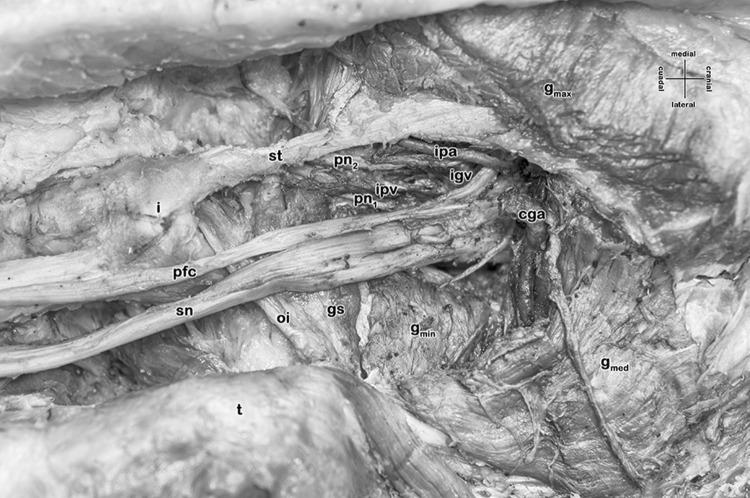

We report a very rare case of a unilaterally absent piriformis muscle in a 60 year old woman. Accompanying variations comprised a common gluteal artery (instead of two distinct superior and inferior gluteal arteries), and an absent gemellus inferior muscle. The contralateral left side showed a normally developed piriformis muscle. In hominoids, the piriformis is constant, but is regularly missing in several other vertebrates. The piriformis muscle is an anatomical landmark for ultrasound investigations and ultrasound-guided interventions in the deep gluteal region such as a superior gluteal nerve block or even a sacral plexus block, also for any surgical approach such as total hip arthroplasty. A missing piriformis muscle therefore affects the orientation in the deep gluteal region and therefore the identification of the targeted structures.

我们报告了一例极为罕见的病例,一名60岁女性单侧梨状肌缺如。伴随的变异包括一条臀总动脉(而非两条独立的臀上动脉和臀下动脉),以及下孖肌缺如。对侧左侧的梨状肌发育正常。在类人猿中,梨状肌是恒定存在的,但在其他几种脊椎动物中经常缺失。梨状肌是超声检查和超声引导下对臀深部区域进行干预(如臀上神经阻滞甚至骶丛阻滞)的解剖标志,也是任何手术入路(如全髋关节置换术)的解剖标志。因此,梨状肌缺如会影响臀深部区域的定位,进而影响目标结构的识别。